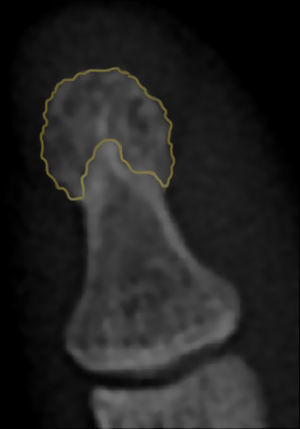

El término acroosteólisis hace referencia a la resorción del penacho de los dedos7, cabe resaltar que el penacho de la falange distal no tiene una definición radiográfica universal, no obstante puede ser considerado como el área de la falange distal en la que la cortical cambia dejando de ser completamente lisa adquiriendo un aspecto lanceolado8 (fig. 1).

Resorción del penacho: pérdida del patrón lanceolado de PFDM adquiriendo una morfología cóncava focal o generalizada con o sin rotura de la cortical.

Esclerosis del penacho: engrosamiento de la cortical del PFDM mayor a 1mm con aumento de la radioopacidad ósea11.

Calcinosis del penacho: calcificación de los tejidos blandos adyacente al PFDM1.